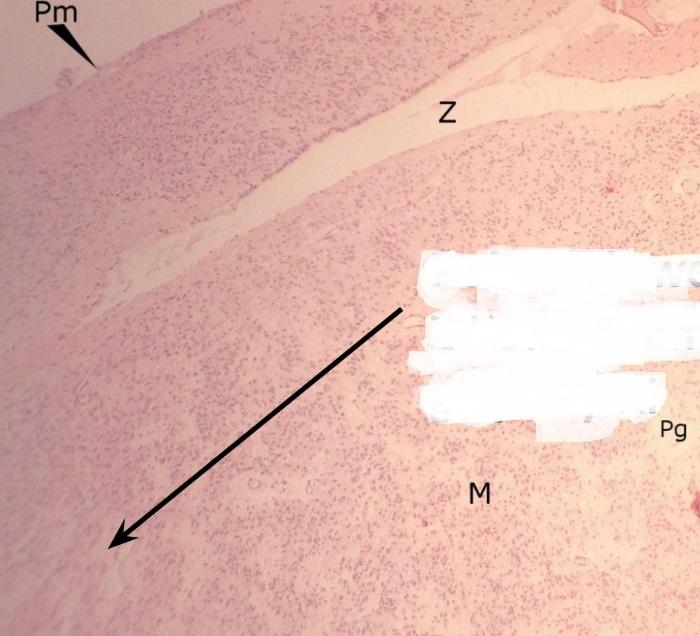

torebka łącznotkankowa (nadnercze)

Pytanie 272

warstwa kłębkowata kory (nadnercze)

Pytanie 273

warstwa pasmowata kory (nadnercze)

Pytanie 274

warstwa siatkowata kory (nadnercze)

Pytanie 275

naczynie zatokowe - małe, podłużne, białe pasmo (nadnercze)

Pytanie 276

żyła nadnerczowa (nadnercze)

Pytanie 277

rdzeń - z feochromocytami (nadnercze)